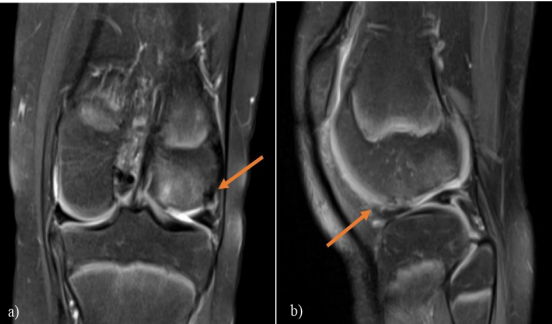

Figura 2. a) RNM T2 de rodilla izquierda, corte coronal, de la paciente donde se aprecia la solución de continuidad a nivel del cóndilo femoral externo de la rodilla izquierda (flecha). b) Corte sagital de la misma rodilla (flecha).

A pesar de la relevancia de las rx, los trabajos de Seelly et al. 6 reflejan que un 44 % de las FOC presentaban rx normales y en el trabajo de Kramer et al. 13 hasta 36% de las FOC no se lograron diagnosticar con rx. Consideramos, por tanto, importante la realización de una RNM en los pacientes que padecieron una LAR, siendo la misma una herramienta imagenológica muy importante en el diagnóstico de estas lesiones, con un 90 a 95 % de especificidad 13. En el caso de la paciente en cuestión, la RNM fue de utilidad en la planificación quirúrgica permitiéndonos valorar la topografía y la magnitud del fragmento osteocondral, así como también nos permitió descartar lesiones asociadas, que pueden tener implicancias terapéuticas.